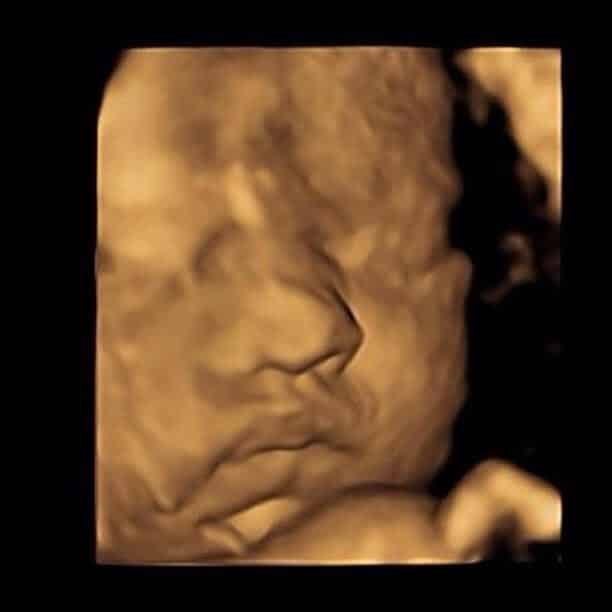

Rose, Gemma, their daughter & bump joined us at our Exeter clinic for a 4D Scan + Fetal Well-being and it was truly a pleasure to welcome them. They took away a diagnostic well-being report, scan movie, photo prints, all digital images through our Bumpies app & more.

“It was a pleasure to welcome Rosie, Gemma and their daughter to our clinic so they could have their full well-being check and see their baby in 4D. It was so lovely to be able to share the experience with them. Despite baby not being in the best of positions at first, after a walk we were able to achieve some fabulous images and we’re pleased they enjoyed their experience and felt so welcome. We’re excited to see photos of baby when they’re born!” Amy, Exeter Clinic Manager

Baby is as cute as a button!

Rose & Gemma 4D Scan